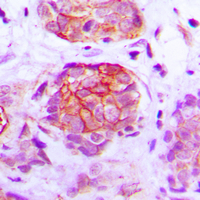

Immunohistochemical analysis of GPR160 staining in human breast cancer formalin fixed paraffin embedded tissue section. The section was pre-treated using heat mediated antigen retrieval with sodium citrate buffer (pH 6.0). The section was then incubated with the antibody at room temperature and detected using an HRP conjugated compact polymer system. DAB was used as the chromogen. The section was then counterstained with haematoxylin and mounted with DPX. -